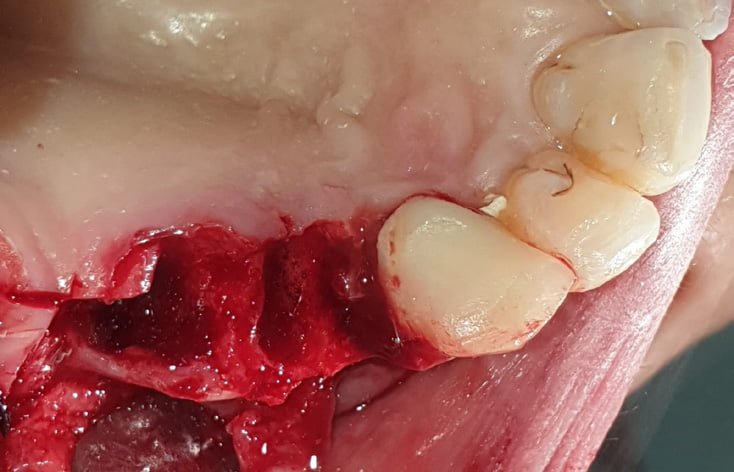

From the first radiographic examination (OPT and CT scan) there is an evident periapical granuloma and pain with pressure on 14 and 15, while 17 element is parodontopathic, moreover there is a lack of bone in 16 and 17 area with chronic infections at the level of the maxillary sinus. Due to the clinical history of the patient it was not advisable to go for a sinus lift, it has been planned the insertion of a pterygo implant and 2 post extractive EV implants. During the surgery, biomaterial (Novocor from B&B Dental) was added to the insertion of the implants to remodel the ridge horizontally, given the evident bone deiescence. Two temporary provisional titanium abutments were then inserted, welded with a two titanium bar. We inserted 2 EV implants to reach a better primary stability. As the patient is bruxist the crowns have been totally unloaded. The pterygoid implant will be loaded on a second session.